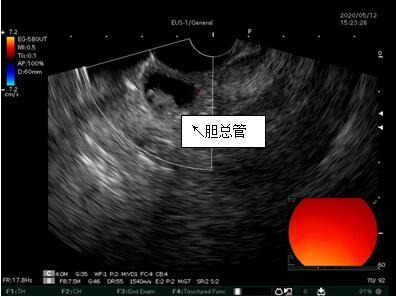

69歲王姓患者,因“發(fā)現(xiàn)無痛性黃疸1月”入院,根據(jù)患者病史,患者診斷傾向于壺腹部腫瘤所致梗阻性黃疸。予以完善腹部CT及上腹部MRI加MRCP均顯示肝內(nèi)外膽管擴(kuò)張,未發(fā)現(xiàn)明顯膽管,胰腺及十二指腸乳頭部腫瘤,且患者CA199正常。以前醫(yī)院未引進(jìn)超聲內(nèi)鏡,這類患者到此就遇到診斷瓶頸。此患者經(jīng)過消化內(nèi)科張丹霞副主任醫(yī)師完善超聲內(nèi)鏡檢查后,可以清楚顯示膽總管下段壁內(nèi)軟組織占位。患者通過超聲內(nèi)鏡檢查診斷明確,轉(zhuǎn)至肝膽外科行手術(shù)治療。

超聲胃鏡圖片

膽總管小腫瘤性病變CT及MRI檢查陽性率偏低,因其低代謝特征,PET-CT陽性率也偏低,超聲內(nèi)鏡對這類疾病的診斷陽性率是所有檢查中最高的,且可行穿刺活檢進(jìn)一步確診病灶性質(zhì)。